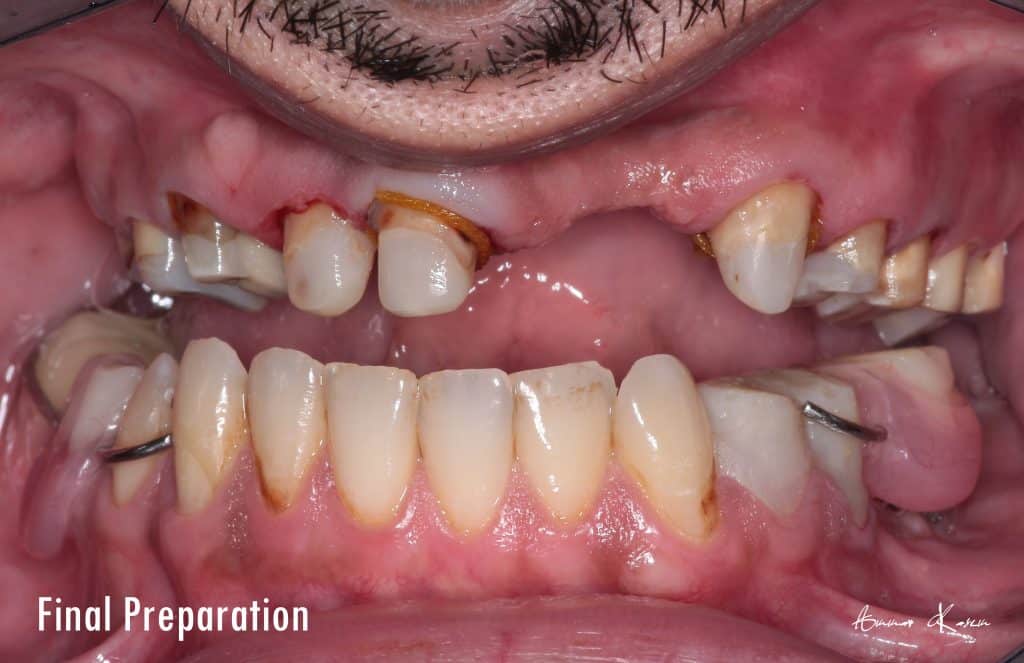

7- Preparation phase through half arch technique to preserve the vertical dimension

2- Restorative phase ( including RCT, post and core )

3- Deprogramming to release stresses and to adjust the new occlusion

4- Facebow records and mounting on semi adjustable articulator